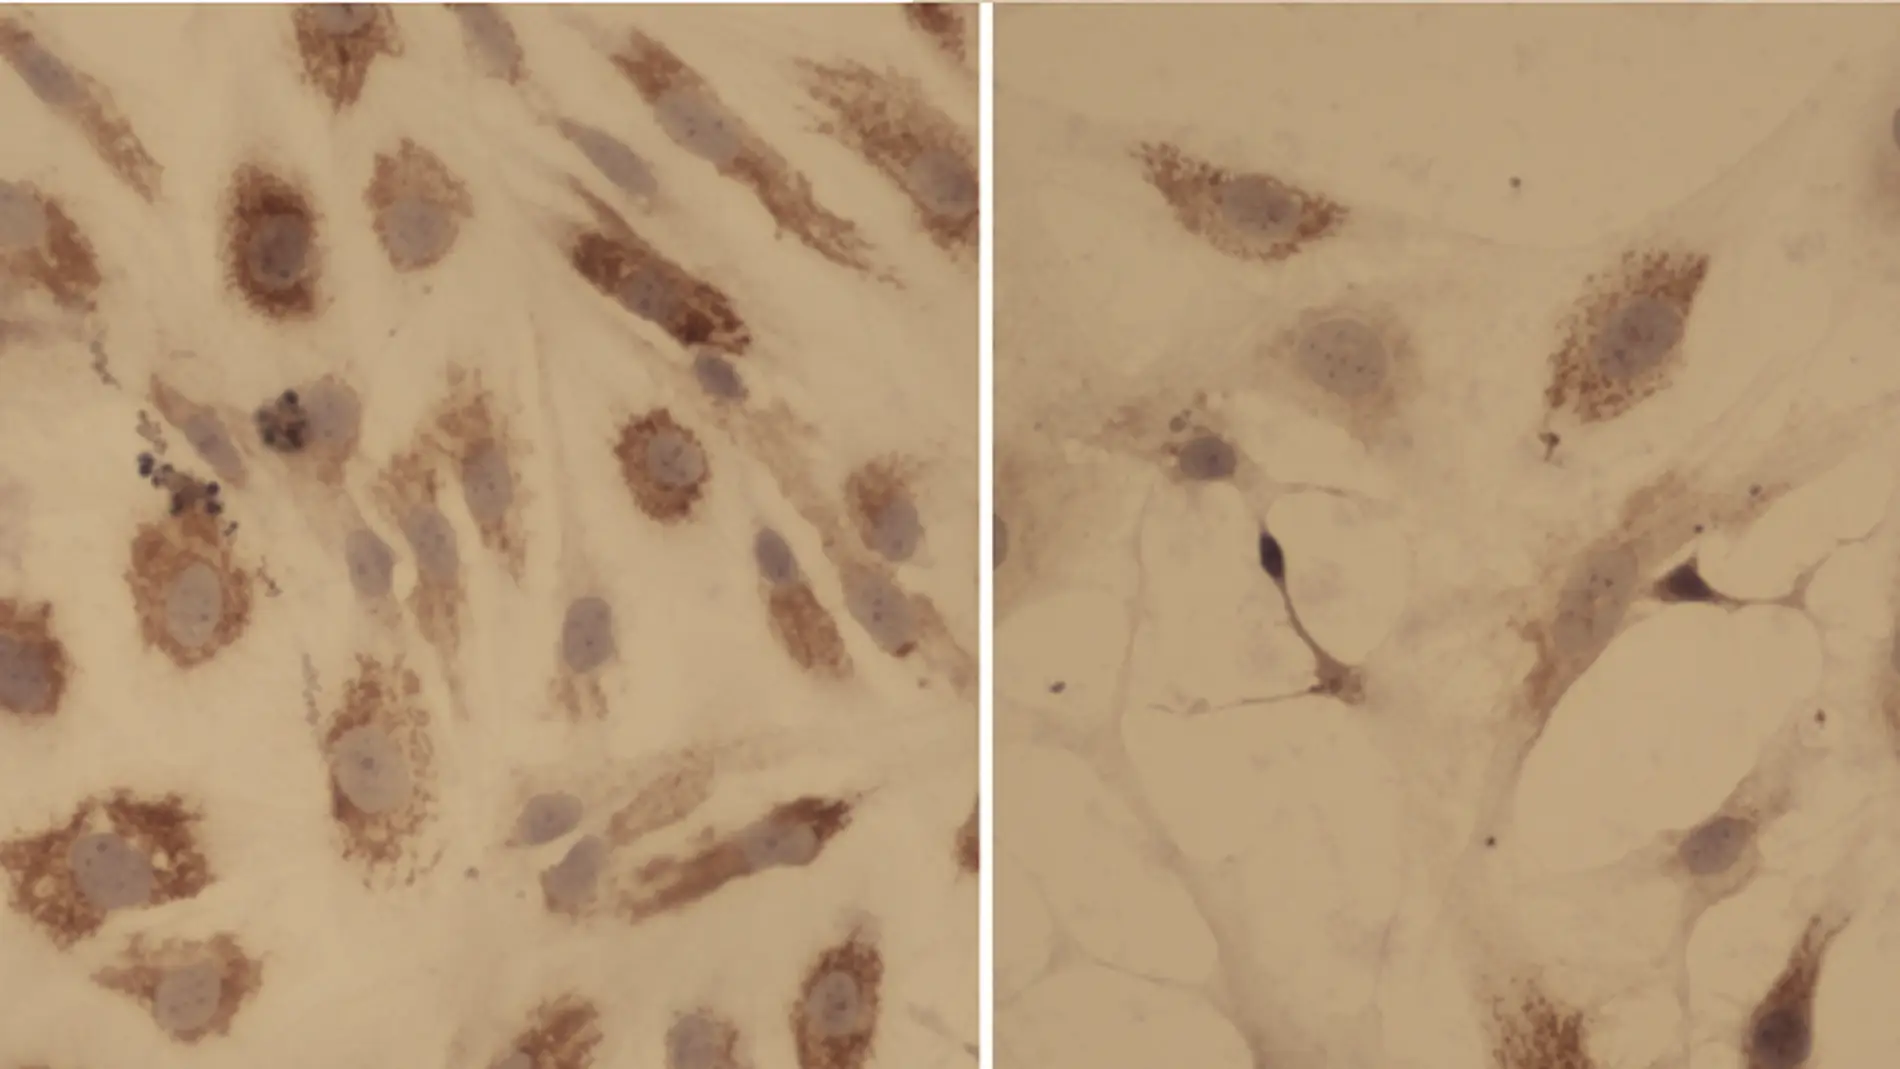

Los investigadores generaron ensayos ex vivo con muestras de pacientes de mielofibrosis y empezaron a exponer a las células a los distintos compuestos, de manera aislada y en múltiples combinaciones. Después midieron la efectividad de cada combinación y estudiaron sobre qué vías biológicas estaba actuando cada compuesto.

Los resultados llegan ahora y son esperanzadores. Revelan que en la triple combinación terapéutica de nilotinib y prednisona, junto con el ruxolitinib, “los fármacos se potencian entre ellos”, explica Gallardo, y se logra así “un aumento de la eficacia” del efecto beneficioso del ruxolitinib.

Tal como explican en Haematologica, los autores atribuyen la mejora a la unión del efecto antifibrótico del nilotinib con la acción inmunomoduladora del ruxolitinib y la prednisona, y el anti-proliferativo del ruxolitinib frente al blasto tumoral. La prednisona es un corticoide; el nilotinib se emplea en el tratamiento de la leucemia mieloide crónica.